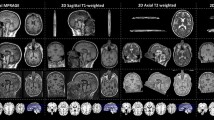

While MRI offers high spatial resolution, providing detailed information on the structure and function of the human brain, this information is multidimensional and complex, resulting in different brain characteristics being examined in isolation. Machine learning reduces this complexity by building statistical models of the brain based on MRI datasets. One example is brain-age prediction, which reduces brain MRI features into a summary score reflecting normative brain health and integrity7. To calculate brain age, researchers train models on large MRI datasets from individuals across different ages. The model learns patterns that predict age from brain characteristics and is then applied to new scans. By comparing predicted and chronological ages, researchers can assess deviations from typical age-related brain structure (see Fig. 1).